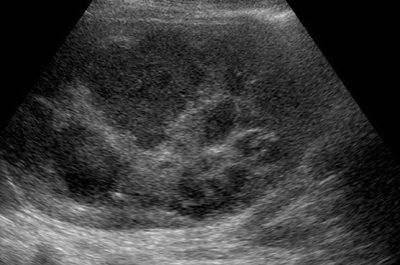

肝膿瘍

肝膿瘍は発熱,悪寒,嘔気,嘔吐,食欲不振,体重減少を伴い数週の経過で亜急性に発症することが多い.急性発症は血行性や経胆道的に生じる多発性の肝膿瘍を示唆する.右上腹部痛は症例の約50%で報告されている.

{化膿性肝膿瘍:多くはE.coliとenterococciが原因とされている.

{アメーバ性膿瘍:Entamoeba histolytica菌体により生じる.

超音波像

内部に液状部分を含む不整形の腫瘤像.液状部分は膿汁の貯留であり,種々の程度に内部エコーを伴っている.この部分が大きければ,後方に音響増強を伴う.